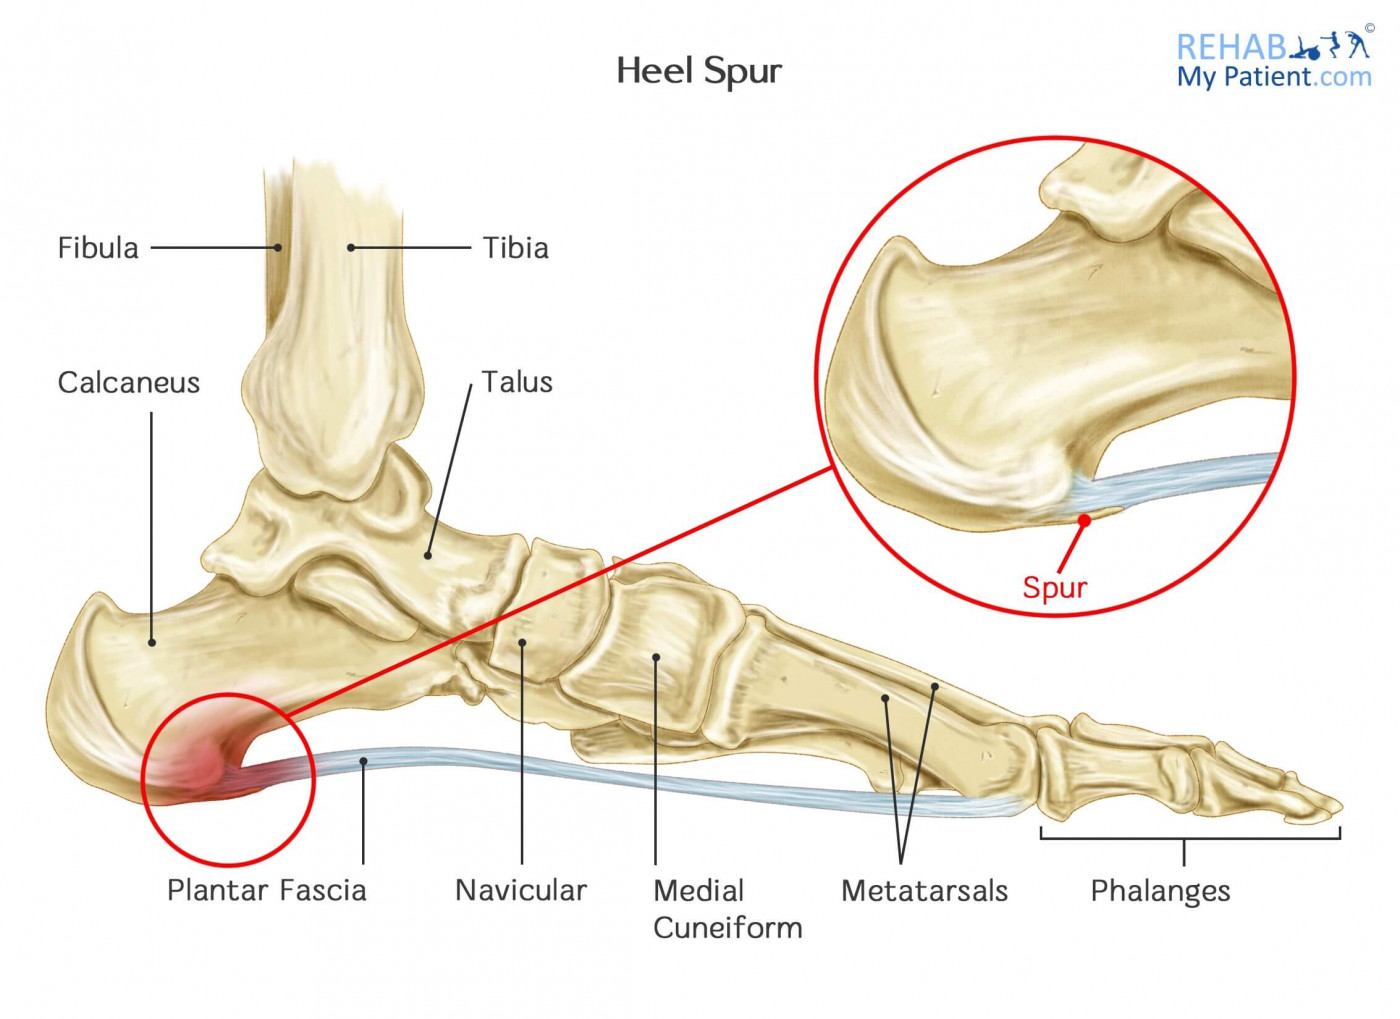

Heel Spur Rehab My Patient